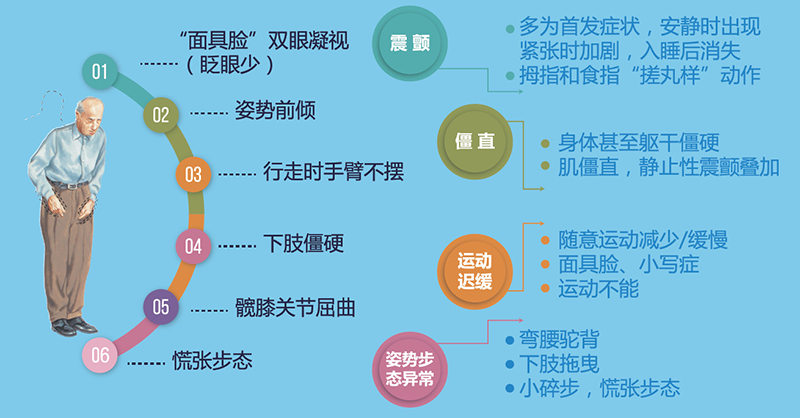

4.11-世界帕金森日不要“帕”,来了解真相

欧洲帕金森病联合会从1997年开始,将每年的4月11日被确定为“世界帕金森病日”。这一天是帕金森病的发现者――英国内科医生詹姆斯・帕金森博士的生日。帕金森病也称震颤麻痹,是一种常见的中老年神经系统变性疾病,我国65岁以上帕金森病标化患病率为1.66%。如今,帕金森病已经成为继心脑血管病、肿瘤之后的中老年第三大“杀手”,...